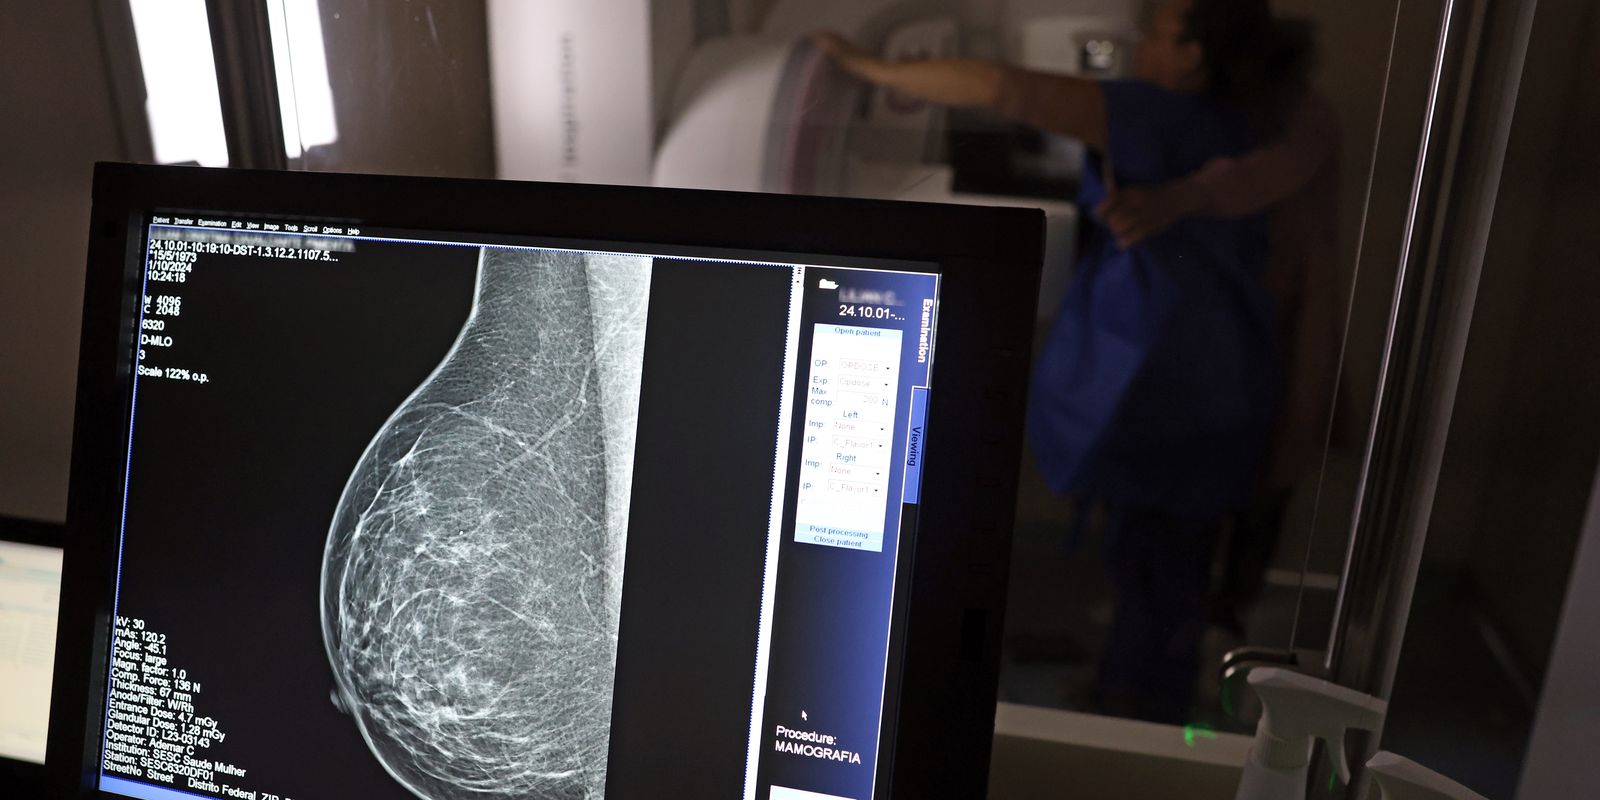

No mesmo local, a dona de casa Lilian Cristina Cavalcanti, fez pela primeira vez uma mamografia, a radiografia específica das duas mamas que possibilita a identificação precoce de alterações nos seios. Com 51 anos e mãe de três filhos, ela admite que, até hoje, deixou a questão de lado por falta de tempo e por achar que seria difícil conseguir a vaga em uma unidade pública de saúde. “Nunca tentei. Não tenho paciência para ficar na fila esperando e, como nunca senti nada [no autoexame da mama], deixei passar”, confessou.

Mas, chegou a hora dela realizar a mamografia bilateral. Lilian Cristina se posicionou em pé, em frente ao aparelho e, imóvel, teve as mamas comprimidas em diferentes ângulos para captura das imagens detalhadas. No fim, ela saiu da carreta do Sesc com impressões positivas sobre o exame. “Achei que doía mais, mas foi bem tranquilo. Agora, espero ansiosa pelo resultado do exame.”

André Abreu, do Sesc-DF, explica que as imagens em alta resolução captadas pelos mamógrafos são enviadas automaticamente aos profissionais do Hospital de Barretos (SP) para análise e emissão do laudo médico, em até 30 dias. “Se o laudador já identificar visualmente um câncer, ele avisará a equipe de Brasília que poderá ter que repetir o exame e esta deverá encaminhar a mulher examinada como paciente ao Hospital de Base de Brasília”. Nos demais casos, quando for constatada a normalidade das mamas, a mulher receberá o laudo em um envelope nominal no prazo citado, no mesmo local – a rodoviária do Plano Piloto.

O técnico em radiologia Ademar Cardoso revelou que, nos dez anos de atuação na área, muitas vezes percebeu a presença de nódulos nas mamas de pacientes ainda no momento de realização da mamografia e comenta a relevância da prevenção. “Muitas vezes vejo pessoas sem informação e, por isso, o exame de graça é tão importante, porque é feito o encaminhamento necessário e a paciente pode dar início a tratamento, quando for o caso.”